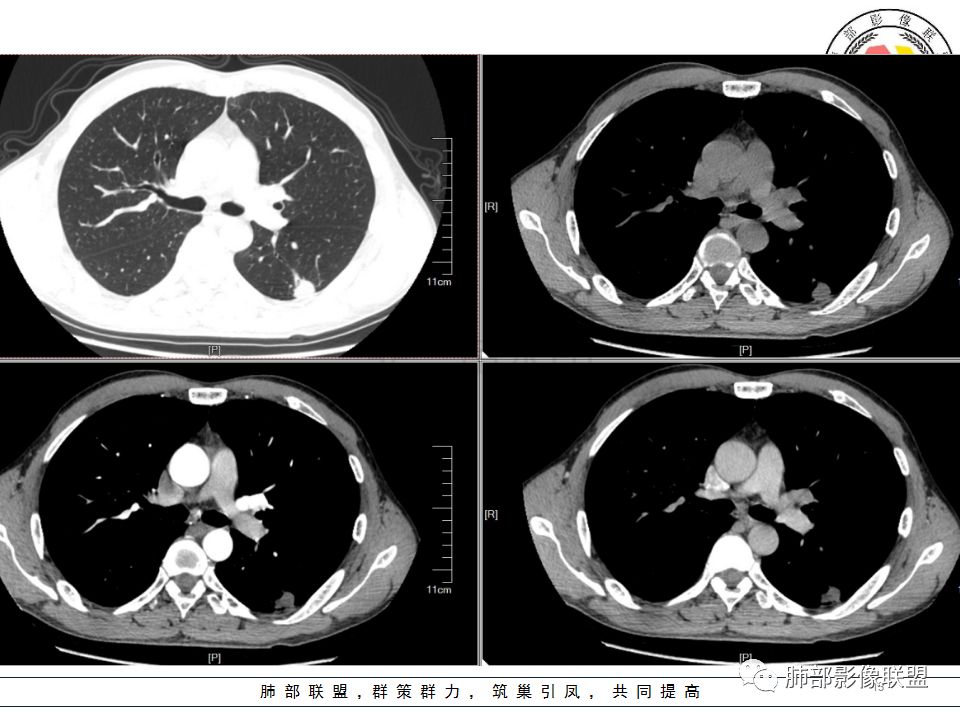

南边:问一个问题:支气管在这里堵了吗

Shelia:堵了,而且支气管壁增厚了。

Coke with ice:我认为堵了,不倾向于肿瘤的堵塞。对于这个病例来说,结核的爬行和肿瘤的堵塞鉴别点不清晰。

南边:这是支气管吗?

张立:是

南边:

远端有支气管显示,提示支气管局部没有堵塞,这个近端的看起来堵塞的支气管可能是假象。

这是我首先把它定在炎性,附近有一些小卫星灶,我还是倾向结核放在前面,待排恶性肿瘤。刚才有老师考虑隐球,这个就不太支持,因为它的长轴是沿支气管过来的,这明显就不是隐球特点。附近有一些小卫星灶,我还是倾向一个结核的可能性大。